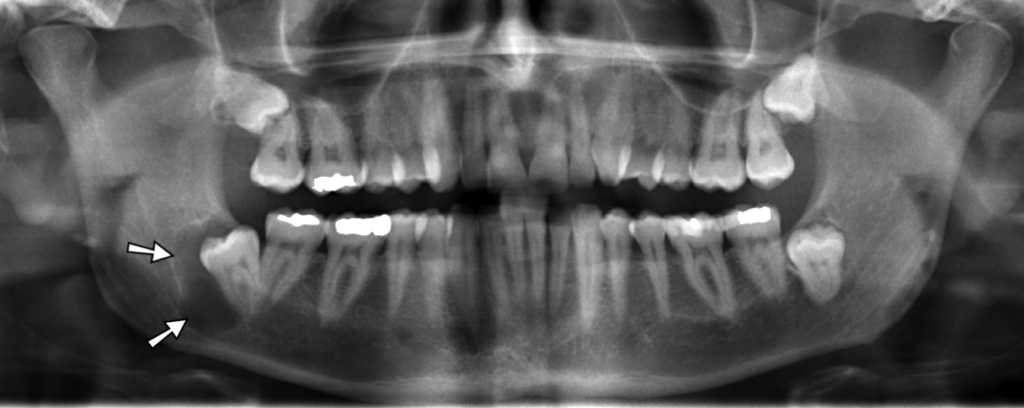

4. 치성 낭종과 종양의 예방 및 치료

치성 낭종 (출처 : 위키피디아)

매복된 사랑니의 경우 간혹 사랑니 치관 주위를 둘러싸고 있는 치아낭(tooth follicle)에 의해 치성 낭종 또는 치성 종양이 생길 수 있으며, 아주 드문 경우 악성으로도 발전할 수 있습니다. 낭종이나 양성종양이라 하더라도 시간이 지나면서 턱뼈를 녹이며 점점 커지기 때문에 이러한 변화가 나타나는 경우 사랑니와 함께 제거가 필요합니다.